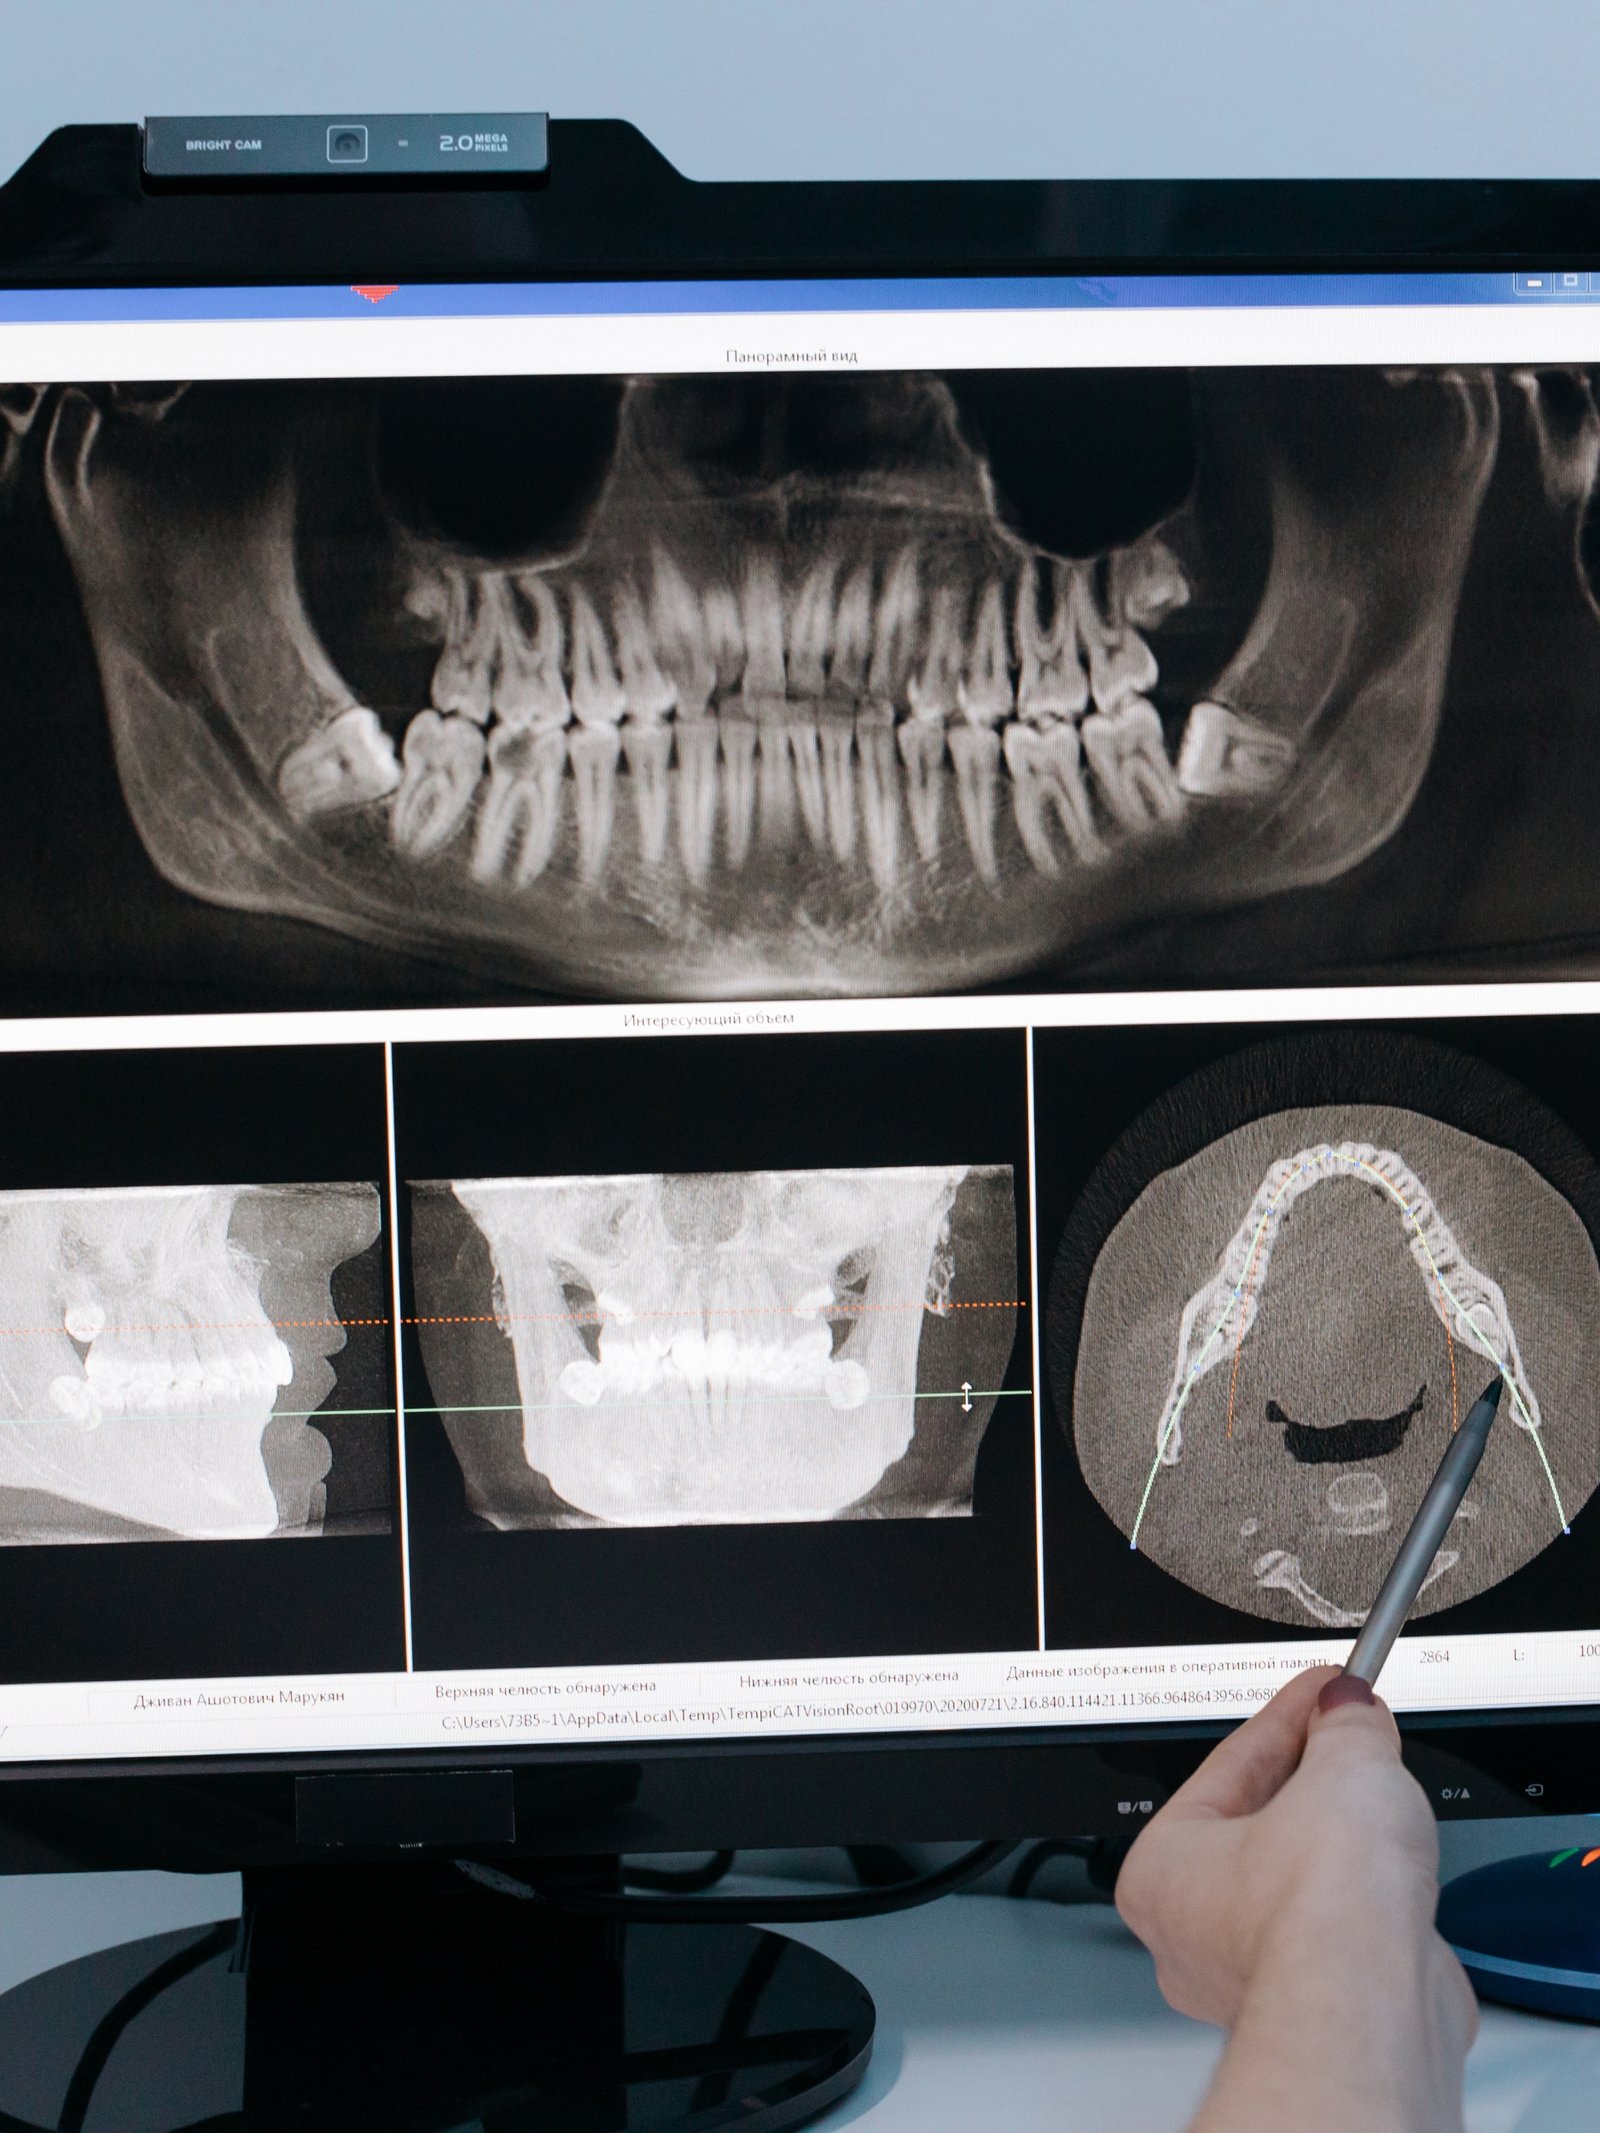

CBCT (Cone Beam Computed Tomography) is advanced 3D dental imaging that shows teeth, bone, nerves, sinuses, and jaw joints in remarkable detail. Unlike traditional 2D X-rays, CBCT eliminates distortion and overlapping structures, helping us see exactly what’s happening beneath the surface.

A pano is 2D and can hide important details. CBCT is 3D, allowing precise measurements and clear views of nerves, roots, sinuses, and bone.